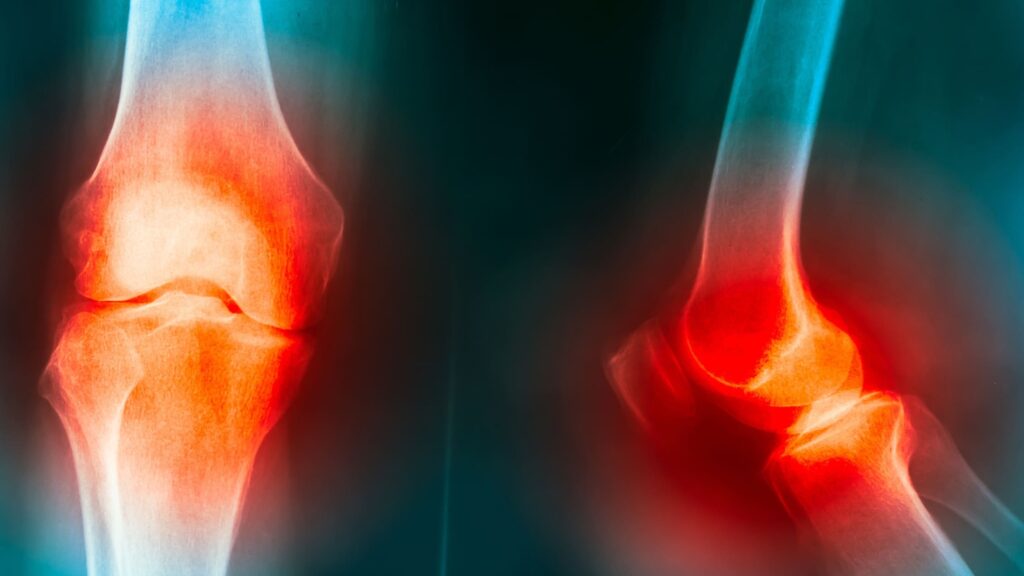

As causas mais frequentes incluem desgaste da articulação (artrose), lesões ligamentares, tendinites, problemas na cartilagem, entorses e sobrecarga por atividades físicas intensas ou repetitivas.

Entre os sintomas mais relatados estão dor localizada ou difusa, inchaço, sensação de instabilidade, rigidez, estalos e limitação para dobrar ou esticar a perna. Em alguns casos, a dor pode piorar com o esforço ou ao permanecer muito tempo parado.